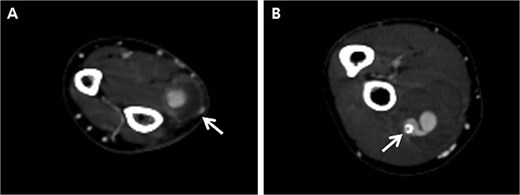

A 66-year-old male with a 1-month prior history of transradial coronary intervention visited hospital for aggravating pain and swelling on the right forearm. Upon physical exam, multiple masses were palpated at the arterial catheterization site as well as another unrelated site at the proximal forearm. An upper extremity CT scan was conducted to evaluate two different RAPs, one at the distal radial artery (arterial catheterization site) measuring 0.8 cm without a neck of pseudoaneurysm (Fig. 1A) and one at the proximal radial artery (Not related to arterial catheterization site) measuring 2.0 cm with a neck of pseudoaneurysm (Fig. 1B). Blood tests for vasculitis or autoimmune disease are not specific to confirm the possible causes of RAPs.

Preprocedural computed tomography of the right upper extremity. (A) Pseudoaneurysm at the distal radial artery which was arterial catheterization site (arrow); (B) Pseudoaneurysm at the proximal radial artery which was not related to arterial catheterization site (arrow).